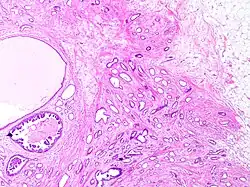

Tubular carcinomas are generally around 1 cm. or smaller, and are made up of tubules. They are usually low-grade.[2] Elastosis has been noted as common but is not present in all cases.[11]

- ^ a b Image by Mikael Häggström, MD. Reference for typical features: Pragya Virendrakumar Jain, M.D., Julie M. Jorns, M.D. "Breast - Other invasive carcinoma subtypes, WHO classified - Tubular". Pathology Outlines.

A highly differentiated invasive carcinoma that forms well-defined tubules (containing epithelium, but no myoepithelium) and that have abundant desmoplastic fibrous stromal reaction between the tubules.